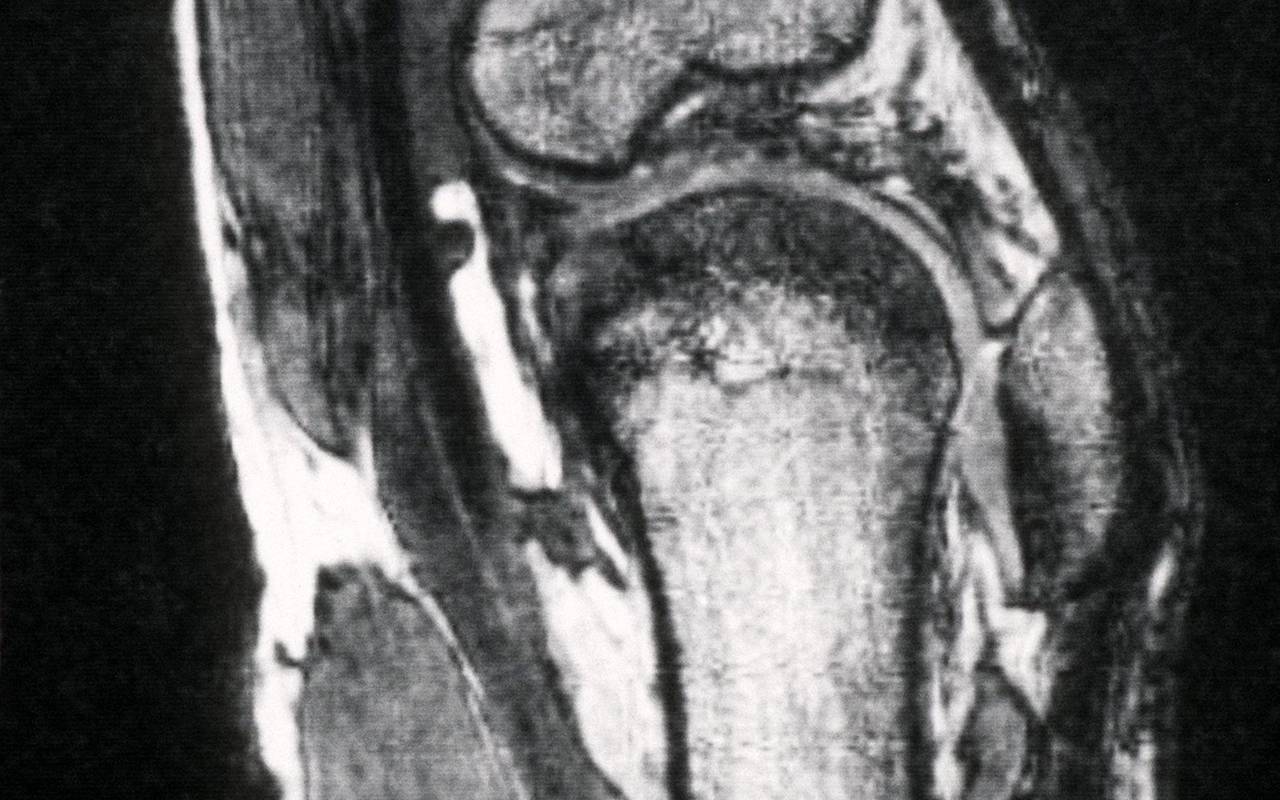

Röntgenaufnahme eines Kniegelenks

Schmerzen im Knie treiben viele Versicherte zum Orthopäden - viele kommen dort mit fragwürdigen Therapien in Kontakt. (Archivbild)© picture alliance / dpa

Schmerzen im Knie treiben viele Versicherte zum Orthopäden - viele kommen dort mit fragwürdigen Therapien in Kontakt. (Archivbild)